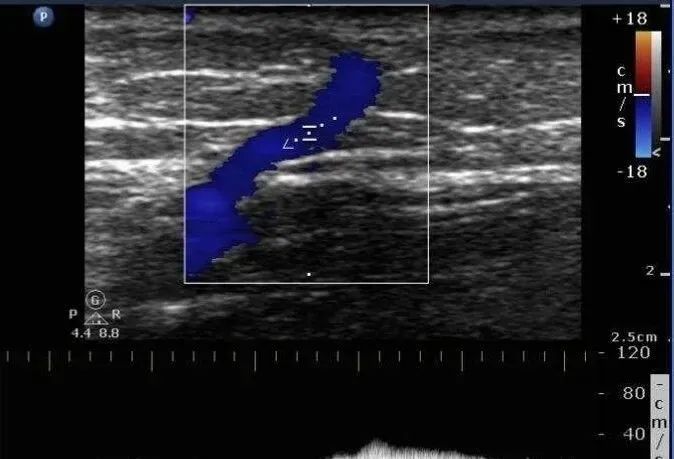

最终,通过B超、血流动力学等专科仔细检查,孟路阳找到了隐藏在皮肤下的已经曲张的静脉。